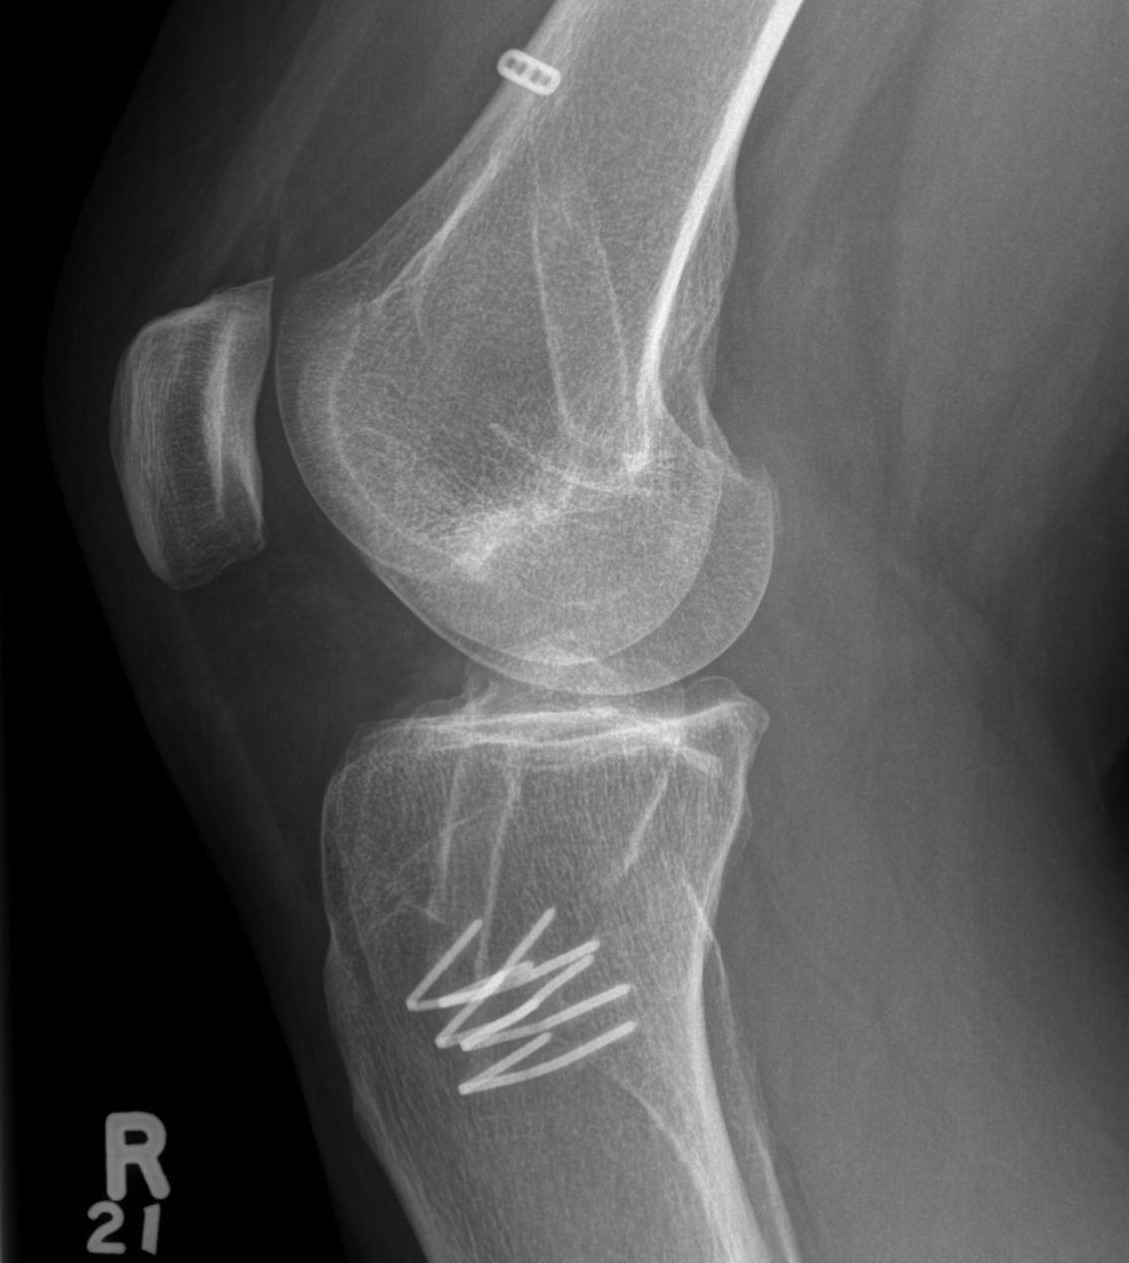

Patient with traumatic failure ACL, previous hamstring with endobutton and bioabsorbable screw

Graft likely too vertical, evidence of tibial tunnel lysis

Old staple had to be removed. Graft passed and fixed on femoral side with 9 x 25 mm screw.

Achilles tendon fixed on tibial side with 9 x 25 screw

Tibial bone very poor and screw little bite (advanced very easily too far into tibia, but not seen in joint).

New staple used, but had to be repositioned as cortical bone soft and fracture easily.